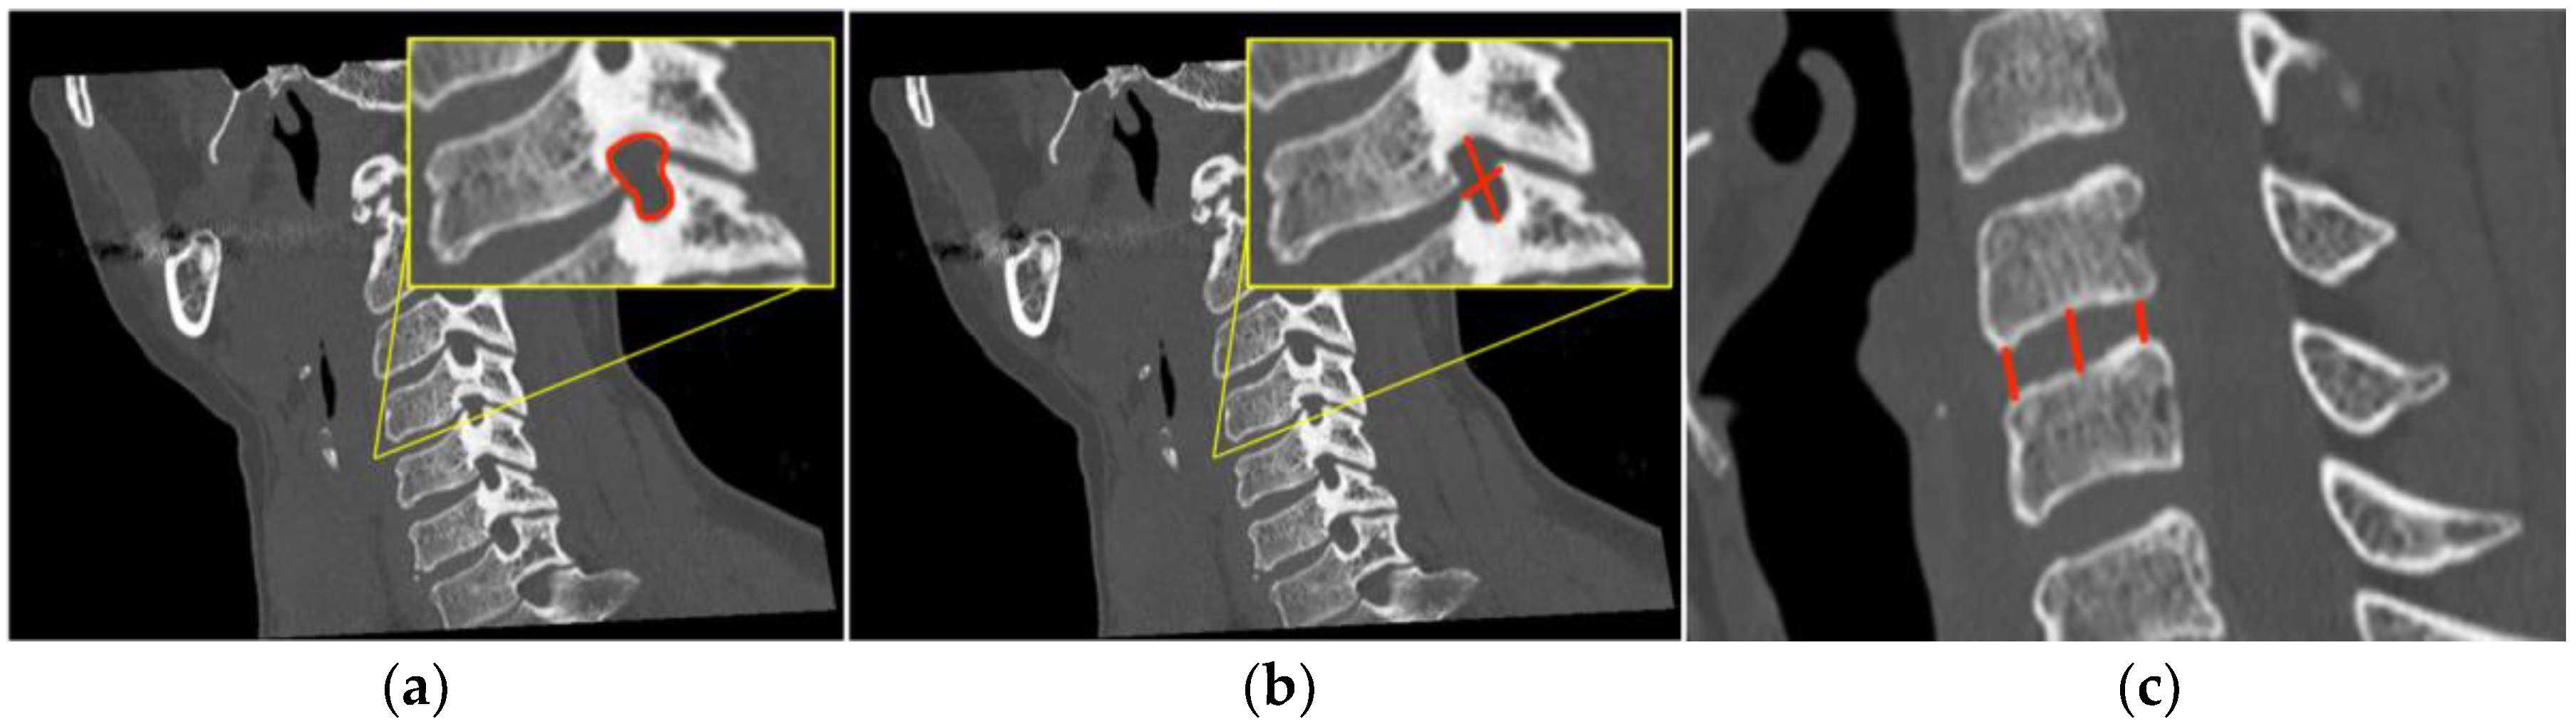

Presenting symptoms included neck pain, radiculopathy and signs of cord involvement without gait impairing 14 patients (Nurick grade 0, I and II) and mild/moderate/severe myelopathic symptoms in 14 patients (Nurick grade III, IV, V or VI). According to mJOA score, no myelopathy was found in two patients, mild myelopathy (mJOA score from 15 to 16) in 10, moderate myelopathy (mJOA score from 12 to 14) in eight, and severe myelopathy (mJOA score from 0 to 11) in 8. An NRS and NDI evaluation between the pre- and post-operative period showed statistically significant results (p value < 0.001). (Figure 3) A negative correlation was confirmed between postoperative clinical outcome and postoperative disc height in its centrum measurement, and specifically −0.468 (p-value = 0.011) with the NRS scale and −0.603 (p-value < 0.001) with the NDI score. Complications of the ACDF procedure are not in the scope of this article, but we found that 60% of patients suffered mild temporary dysphagia and 15% suffered from slight temporary dysphonia. No postoperative hematomas or cage displacement were documented in our series. No permanent deficits were recorded, and temporary disturbances progressively regressed before discharge. An illustrative case is shown in Figure 4, comparing pre- and post-operative results. Table 4 shows patients’ demographic data, disease level, clinical pre- and post-operative grade, and a brief description of onset symptoms.

Figure 4. Case illustration. Pre-(a, yellow box) and post-(b, red box) operative comparison of the foramen height (C-C diameter) at C4-C5, on the right side for illustrative purposes only, after the implant of a single-level cage.